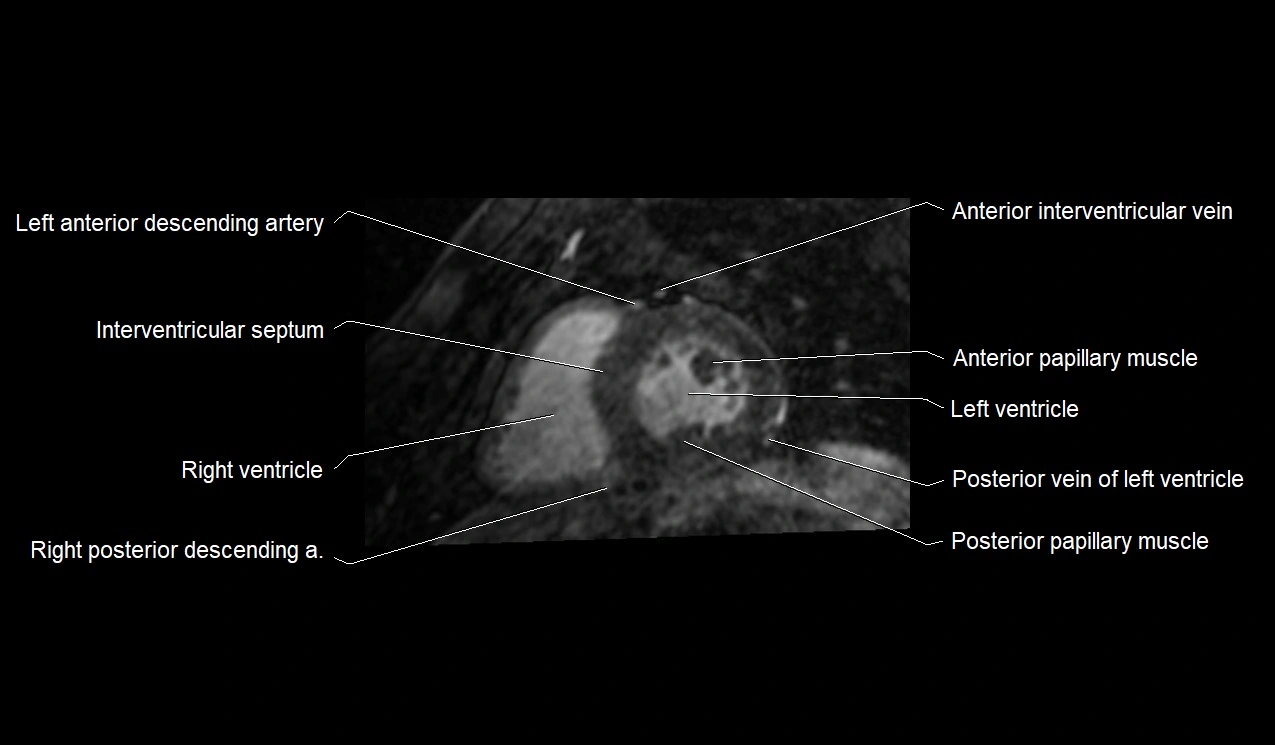

MRI image